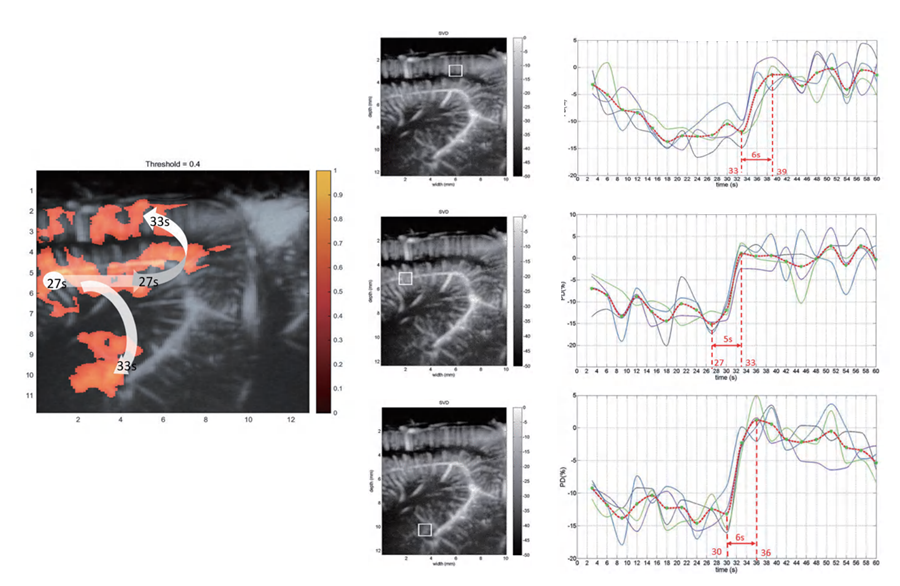

刺激小鼠胡须引起脑功能活动

血流变化监测:大脑不同区域的血流在活动时会发生变化,功能性超声技术可以实时检测这些血流变化,从而反映大脑各个区域的活跃程度

脑功能与血流关系:大脑活动增加时,相关区域的血流会增强。通过监测这些变化,可以了解大脑在执行不同任务时的活动模式